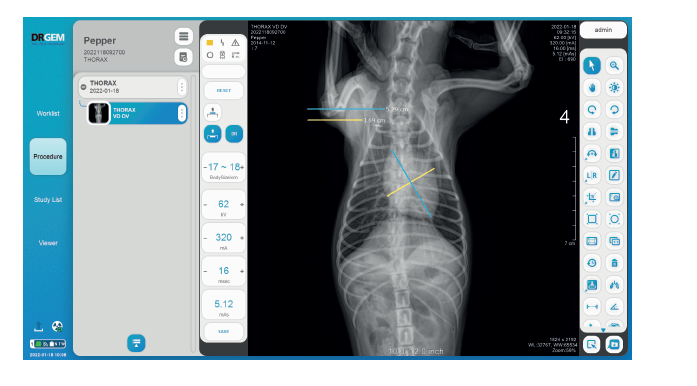

Whether it is a retrofit or a full integration, it will speed up your scanning process and optimize your busy workflow

It will help you Improve diagnosis by better visualization of the anatomical structures at a much lower dose